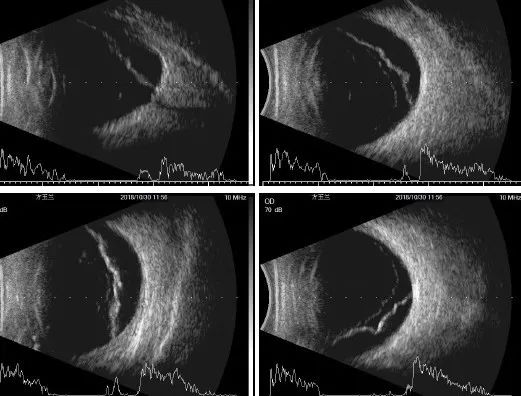

术前B超

方阿姨被收住院后,由我负责。当时给她检查后,我的感觉是这只眼睛存在各种异常,眼球震颤、角膜白斑、白内障,现在又加上视网膜脱离,眼底根本看不见,很难做手术,术后也不见得有视力。万一有并发症,或者效果不理想,容易引起患者的抱怨和迁怒,得不偿失。怀着这种想法,我把患者病情告知了正在手术的陈楠主任,她似乎也同意我的观点,说:“等我回来后看看,动员患者不要冒风险了吧。”就这样,我松了一口气,病情这么复杂的患者,就要出院了。

虽然角膜可见度差,但在陈楠主任的“妙手”下,手术过程始终按部就班地顺利进行着,而这都依赖于周密的手术计划、充分的准备和高超的手术技巧。术中剪除前粘的虹膜,开大瞳孔,摘除白内障,发现眼底为高度近视改变,确实视网膜脱离,而且是要求最为精细的黄斑裂孔性视网膜脱离……1小时后手术结束,视网膜成功复位。术后观察3天,一切反应良好,患者能够自己走到检查室,坐到凳子上做检查。这时我才知道,这么糟糕的眼前节病变,也能做视网膜手术。